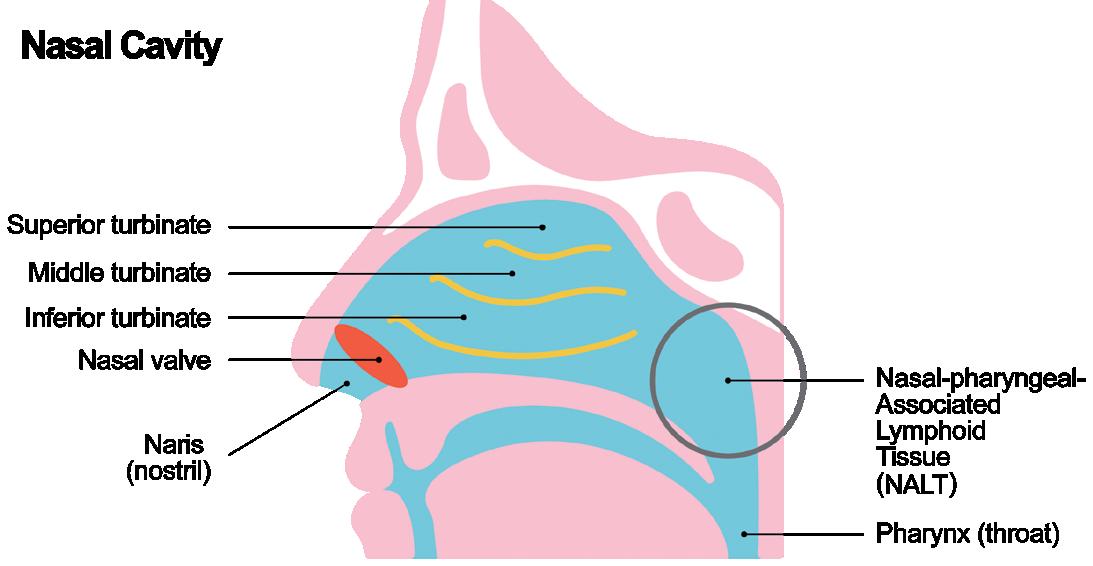

Addressing CNS Therapies Through Nose-to-Brain Pathways

Alain Regard, Technology Product Manager;

Raphaële Audibert, Marketing Category Manager – Ear Nose Throat; and Audrey Chandra, Marketing Category Manager

Nemera

Interview – Exploring Nasal Casts in Nasal Drug Development

Julie Suman, Vice-President, Scientific Affairs

Aptar Pharma

How to Choose the Right Intranasal Vaccine Device

Nia Stevens, Consultant Mechanical Engineer

Team Consulting

The Path to Nasal Drug Product Commercialisation

Eric Kaneps, Vice-President of Sales & Marketing

Renaissance Lakewood